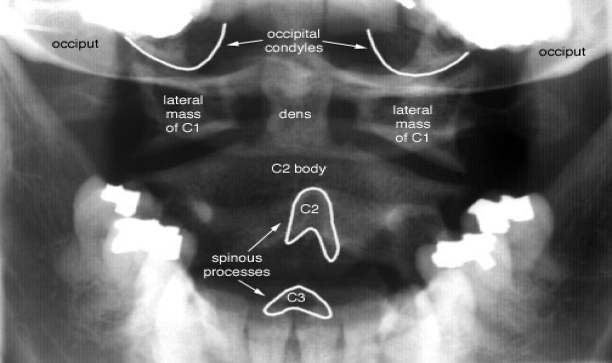

Cervical Spine

Radiographic evaluationOpen mouth odontoid